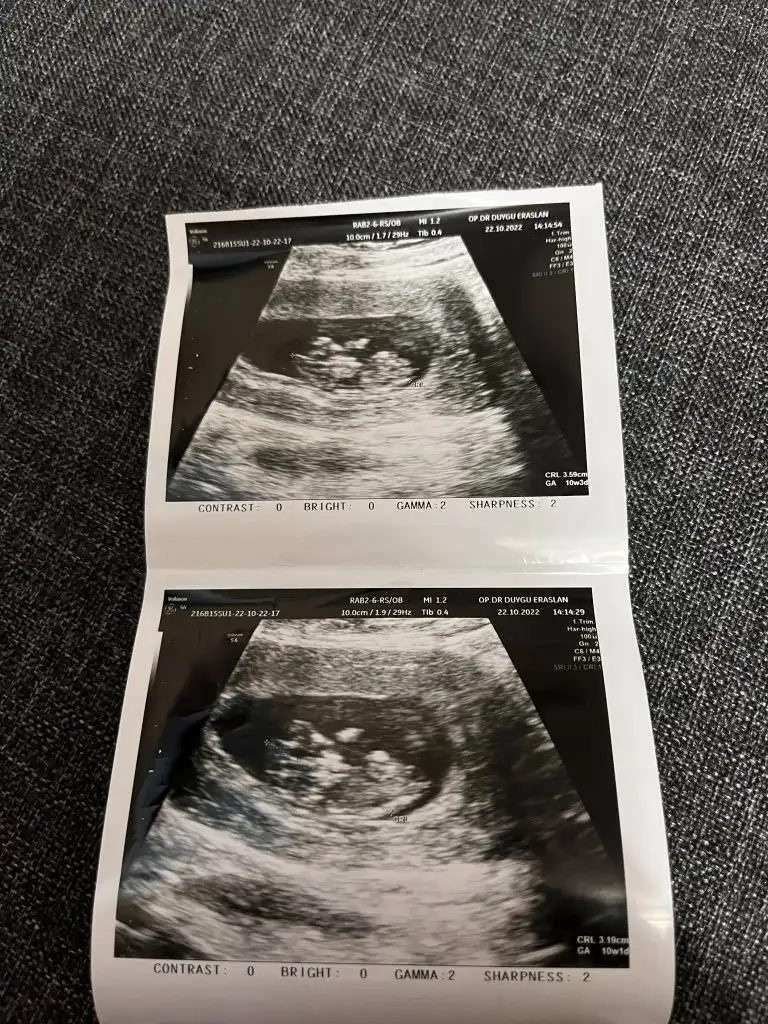

Merhaba bebeğim 10 haftalık. Benim içinde yorum yapar mısınız. teşekkürler <3Selam Kızlarbir çok kişi gruplardan beni bilir. Yine yetiştim imdatlara

Buda usg lerimSelam Kızlarbir çok kişi gruplardan beni bilir. Yine yetiştim imdatlara